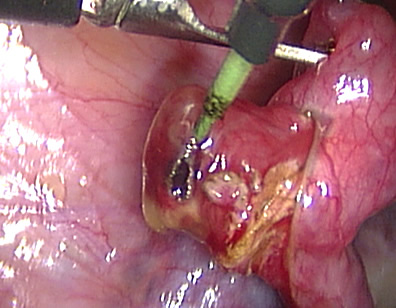

The products of conception are removed completely from the tube.